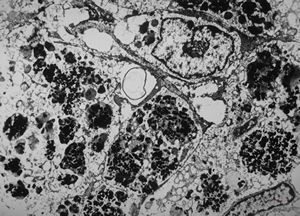

oral saprophytic bacterium